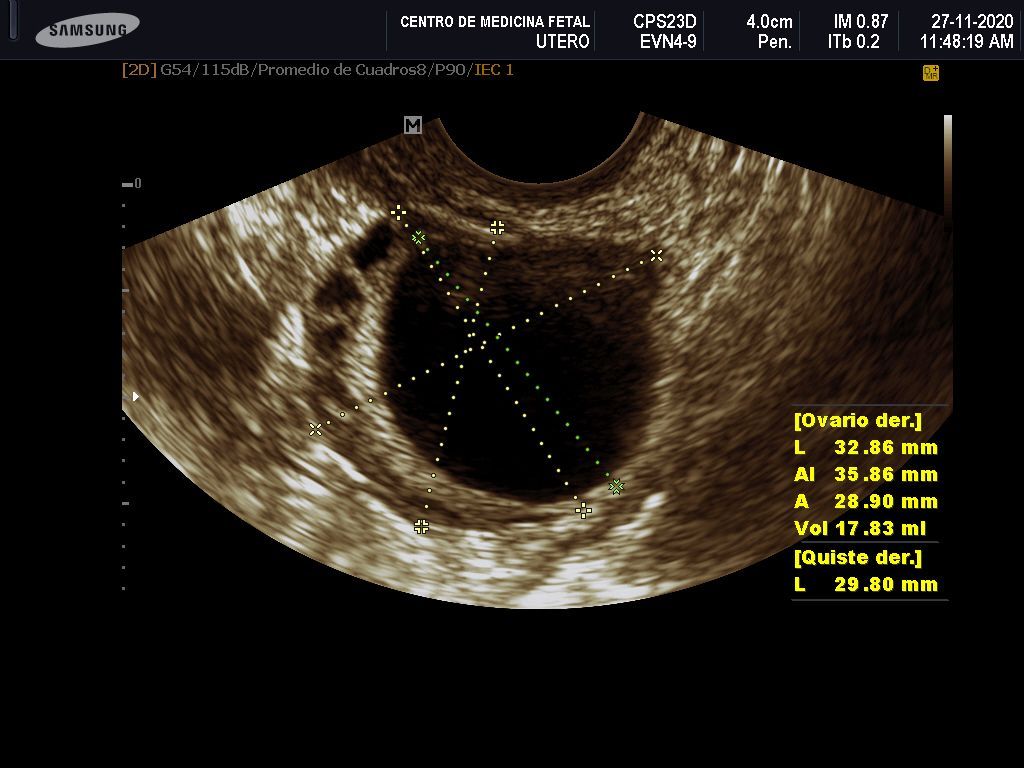

- Detección ecográfica transvaginal o pélvica y tratamiento de: Miomas, quistes de ovario, endometriosis, malformaciones uterinas